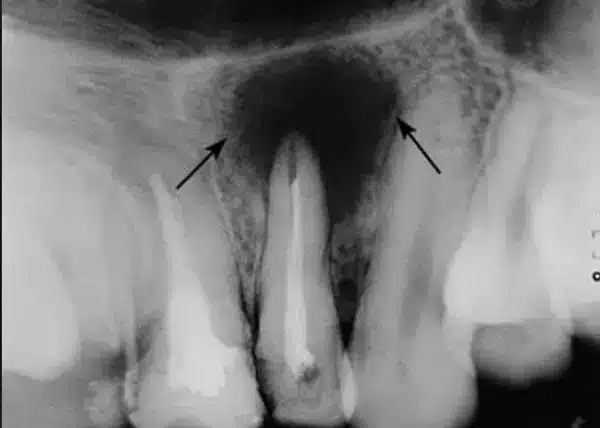

Si antes de hacer la endodoncia el hueso circunscrito al ápice dental presentaba un aspecto saludable, al pasar unos meses podemos observar en la radiografía una imagen radiolúcida, oscura, en la punta de la raíz del diente endodonciado que nos indica que hay lesión ósea.